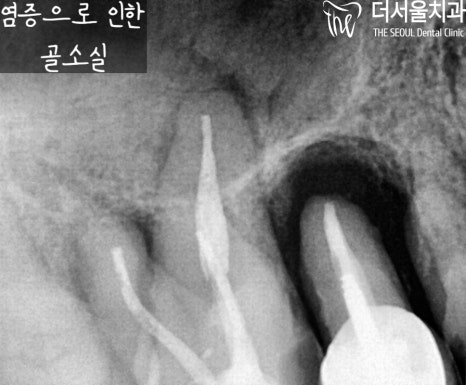

우선 10번대를 살펴보면 치근단 염증으로

뿌리 끝에 거멓게 변해있는 것을

볼 수 있으실텐데요.

이미 골소실이 많이 일어났고,

그 영향으로 이가 흔들릴 수밖에 없었습니다.